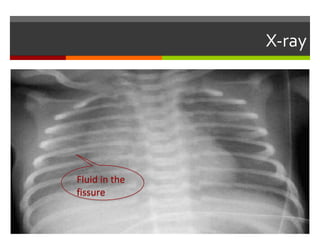

TransientTachypnea of Newborn

Chest x-ray :

 Prominent perihilar streaking (due to engorgement of

periarterial lymphatics)

 Fluid in the minor fissure

 Prominent pulmonary vascular markings

 Hyperinflation of the lungs, with depression of

diaphragm

 ► Chest x-ray usually shows evidence of clearing by 12-

18 hrs with complete resolution by 48-72 hrs

chest X-ray:TransientTachypnea of Newborn

Fluid in the

fissure